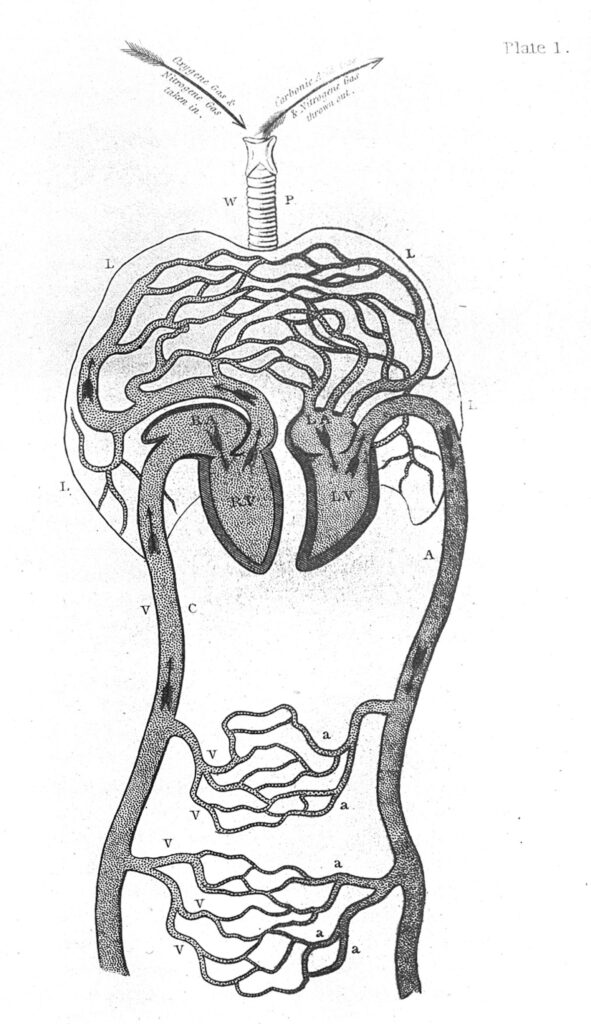

–Mejor le describo mis procedimientos. La terapia que yo le doy a las personas consiste en producir un nivel de asfixia que produce placer. Seguramente usted ha escuchado algo de eso. Los psiquiatras lo consideran una parafilia y una práctica de riesgo, pero en mi experiencia he podido observar que se puede alcanzar un dominio que le permite a los pacientes llegar a una epifanía. Antes de empezar la terapia, analizo la complexión, el estado de salud y otros aspectos físicos del paciente para estimar qué tanto puede resistir el procedimiento, es decir, qué tanta fuerza puedo ejercer, porque mi técnica es el estrangulamiento.

–Sí, sólo utilizo mis manos y dejo que el cuerpo de mis pacientes me vaya diciendo hasta qué punto llegar. Hay quienes necesitan poco, otros mucho más, pero siempre trato de evitar ponerlos al límite de sus condiciones de salud. Al final, ellos encuentran en esta situación una forma de enfrentarse a sus problemas. El extremo al que los llevo y la vuelta en sí mismos, una vez que lograron el orgasmo, les permite ver que pueden superar aquello que los ahoga en sus vidas, y que además les puede resultar placentero. Por eso le digo que la terapia es una mezcla de saber médico y fe.

–Por desgracia, sí. Tal vez sus problemas eran insuperables y no pudo dar el salto de fe. No conseguía eyacular. Eso me llevó a aplicar más fuerza y terminé perdiendo el control.